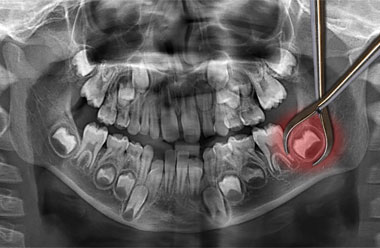

Souvent, ces dents ne font leur apparition dans la bouche que de façon partielle, ou alors elles n'apparaissent jamais. Autrement dit, elles restent semi ou totalement incluses dans la gencive.

Les dents de sagesse, en particulier les inférieures, sont de loin celles qui prennent le plus souvent une position anormale dans l'os. Elles peuvent alors un jour s'infecter ou apparaitre en déplaçant ou en endommageant les dents voisines.

- Si présence d'infection ou d'un kyste entourant la dent de sagesse

- Si la dent est impactée